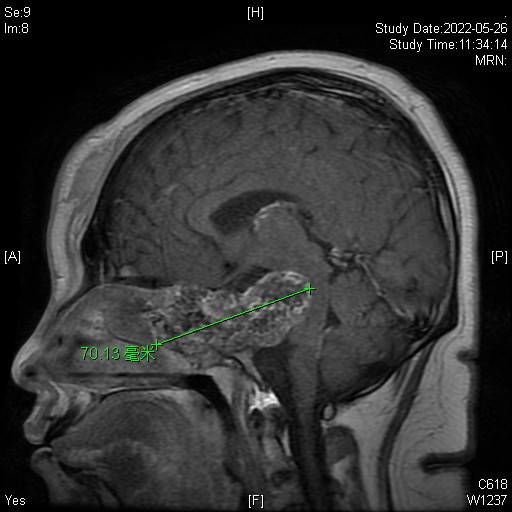

1.女性患者,31岁,头痛、下肢无力10天。

2.体检: 右耳听力下降;左眼不能外展,左侧上肢肌力5级,左侧下肢肌力3级。

3.辅助检查:鼻咽CT增强扫描蝶骨体骨质破坏,局部形成巨大软组织肿块,内见散在钙化,前后径约64mm,左右径约47mm,左侧颞叶受压,向后压迫桥脑,向前突入筛房,前颅窝底骨质破坏。

3.诊断:软骨肉瘤?